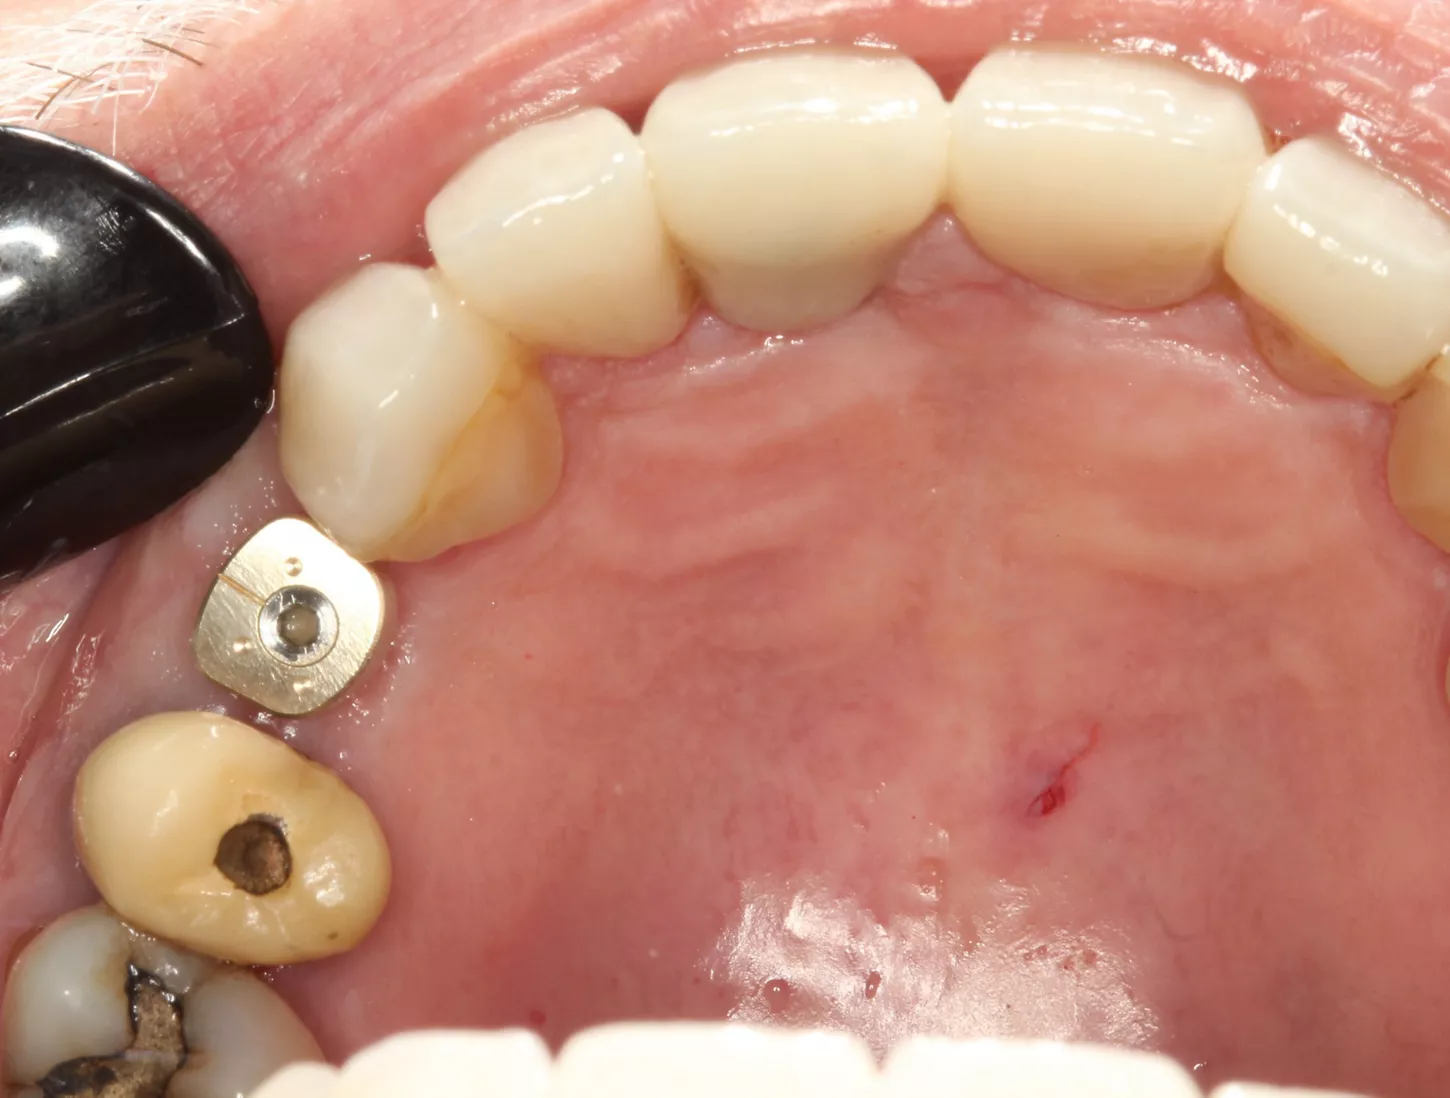

7. Distal implant placed with a cover screw, and mesial implant restored with a HealFit® SH anatomical healing abutment.

7

Suturing was adapted to each implant site. The distal implant was fully submerged with a cover screw, requiring complete primary closure. At the mesial implant, where a HealFit® SH abutment was placed, only two simple interrupted sutures were placed mesially and distally to stabilize the soft tissues.

8. Suturing was adapted to each implant site. The distal implant was fully submerged with a cover screw, requiring complete primary closure. At the mesial implant, where a HealFit® SH abutment was placed, only two simple interrupted sutures were placed mesially and distally to stabilize the soft tissues.